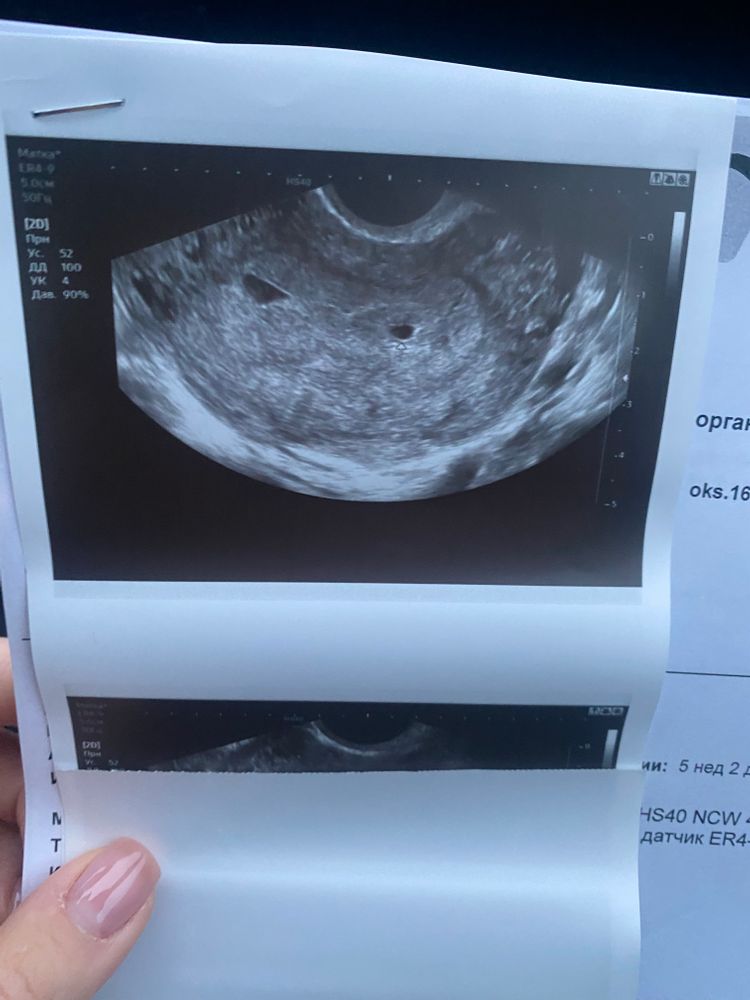

Плодное яйцо неправильной формы, полость матки расширена

Полина Викторовна , да, я очень рано пошла в первый раз не узи.. не нужно было. Сделала это чтобы исключить внематочную, а возникло еще больше вопросов. Вот прикрепила фото..

Изображение Изображение Изображение